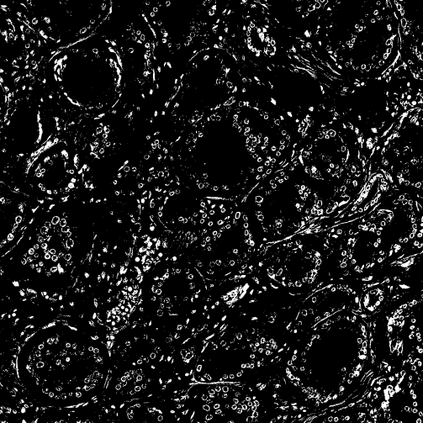

Pathologists diagnose and grade prostate cancer by examining tissue from needle biopsies on glass slides. The cancer's severity and risk of metastasis are determined by the Gleason grade, a score based on the organization and morphology of prostate cancer glands. For diagnostic work-up, pathologists first locate glands in the whole biopsy core, and -- if they detect cancer -- they assign a Gleason grade. This time-consuming process is subject to errors and significant inter-observer variability, despite strict diagnostic criteria. This paper proposes an automated workflow that follows pathologists' \textit{modus operandi}, isolating and classifying multi-scale patches of individual glands in whole slide images (WSI) of biopsy tissues using distinct steps: (1) two fully convolutional networks segment epithelium versus stroma and gland boundaries, respectively; (2) a classifier network separates benign from cancer glands at high magnification; and (3) an additional classifier predicts the grade of each cancer gland at low magnification. Altogether, this process provides a gland-specific approach for prostate cancer grading that we compare against other machine-learning-based grading methods.